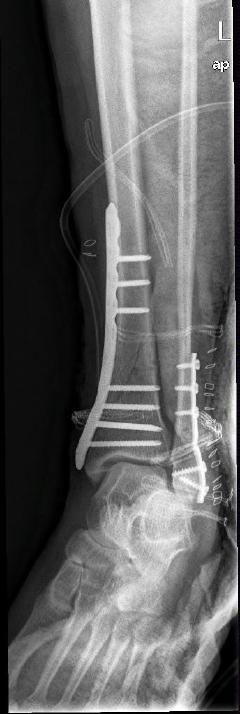

Περίπτωση 2ου ασθενούς

Με τα σύγχρονα μέσα που διαθέτουμε, όλα σχεδόν αυτά τα κατάγματα πρέπει να αντιμετωπίζονται χειρουργικώς. Υπάρχει πληθώρα υλικών οστεοσύνθεσης (πλάκες διαφόρων τύπων, ενδομυελικοί ήλοι, συστήματα εξωτερικής οστεοσύνθεσης) που είναι διαθέσιμα και επαφίεται στην εμπειρία του χειρουργού η επιλογή.

Οπως και άλλοι εξοικειωμένοι χειρουργοί διεθνώς, χρησιμοποιώ τεχνικές ελάχιστης παρέμβασης (Minimal Invasive Surgery), δηλαδή μικρές τομές, επειδή έτσι το χειρουργικό τραύμα είναι ελάχιστο, με αποτέλεσμα ταχύτερη επούλωση. Ταχύτερη πώρωση των καταγμάτων, ταχύτερη κινητοποίηση.